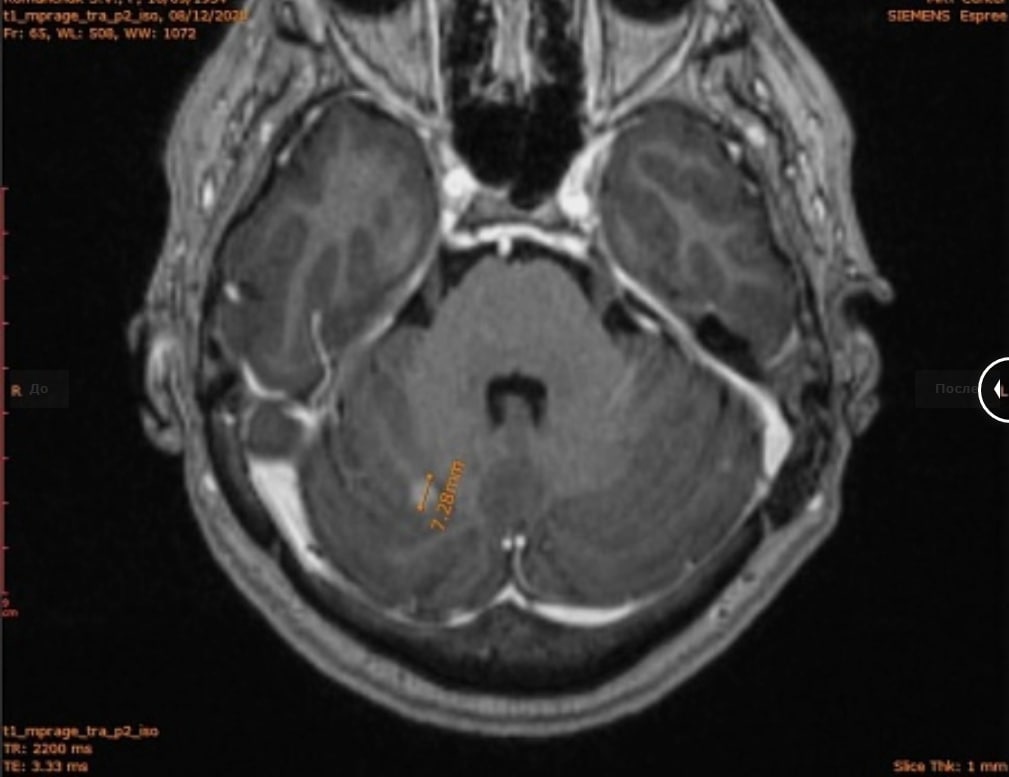

В 2020 году у пациентки появилась мозговая симптоматика. Один из главных симптомов – нарушение координции движений. В декабре врачи назначили ей МРТ головного мозга и нашли на нем очаг в мозжечке. Мозжечок – отдел головного мозга, который отвечает за координацию движений.

1 ферваля 2021 года на контрольном МРТ-исследовании головного мозга очаг в мозжечке исчез. А по заключению радиолога из МНИОИ им Герцена от 05.02.2021 стало ясно, что проведение ДЛТ на весь обьем головного мозга не показано.